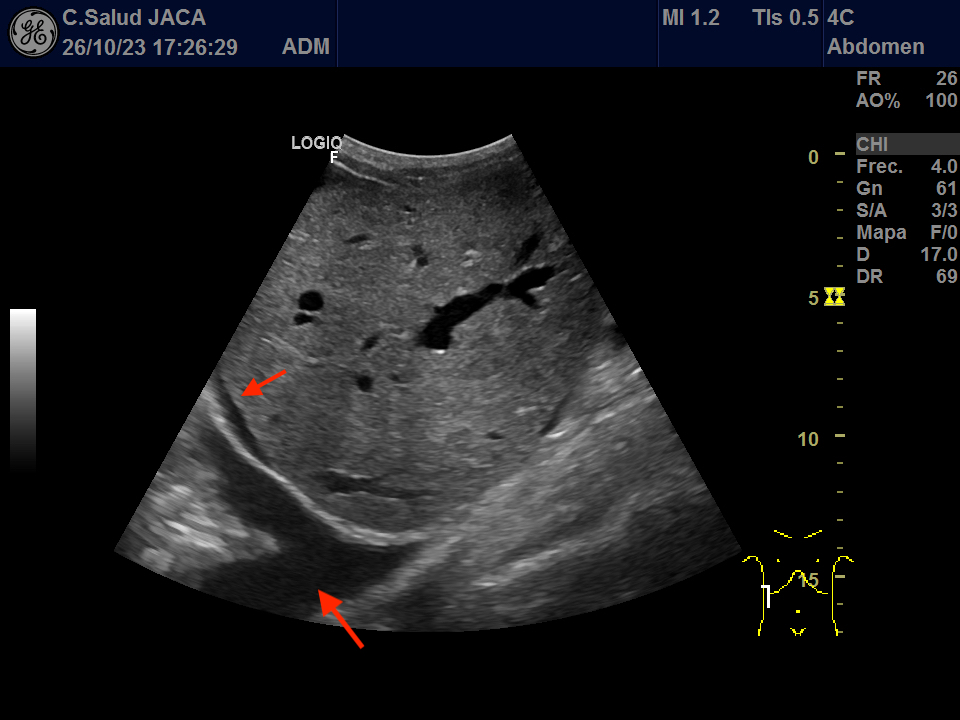

Presentamos las ilustrativas imágenes ecográficas obtenidas con sonda convex en la consulta de su Médico de Familia, que muestran derrame pleural y pericárdico, gran dilatación de ambas aurículas (ventana subxifoidea), ascitis, engrosamiento de 30 mm de la cava a su entrada en la aurícula derecha, que no se modifica con la inspiración, y congestión igualmente de las venas suprahepáticas.